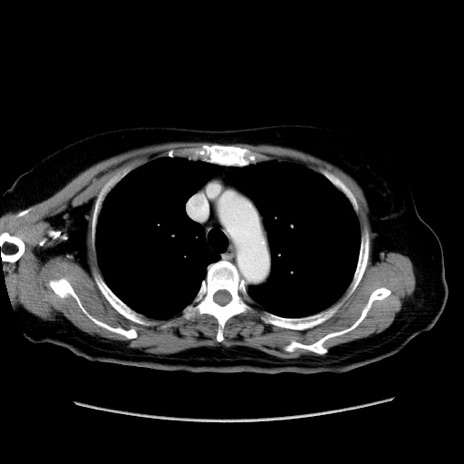

症例19(横断像)

【症例】80歳代女性

【主訴】下腹部痛

【現病歴】約8時間前より下腹部痛の出現あり、救急外来受診。

【既往歴】両側付属器切除

【身体所見】意識清明、下腹部正中に手術痕あり、その部位に一致して圧痛と反跳痛あり。腸蠕動音は亢進。

【データ】WBC 9300、CRP 0.15